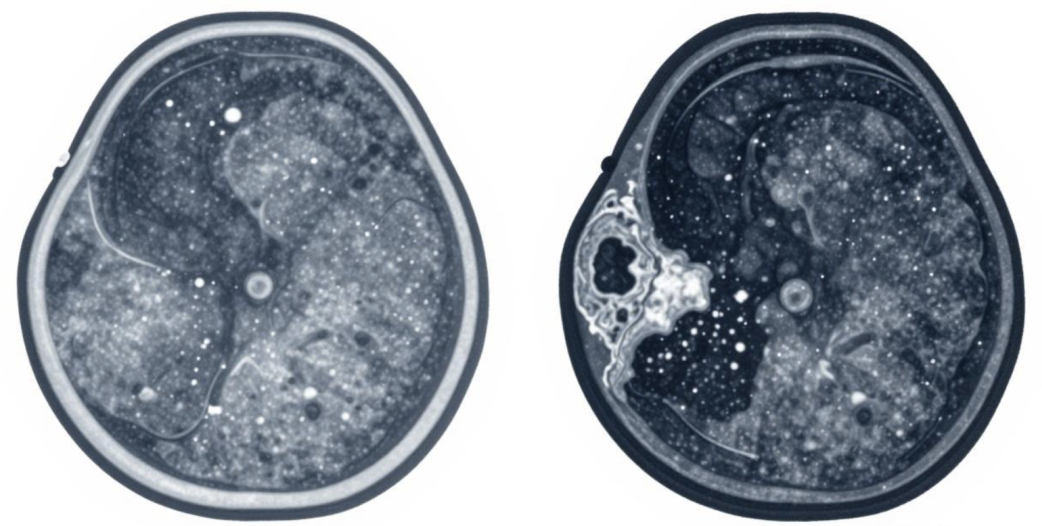

乳腺结节的大小,只能说明结节的尺寸,和良恶性没有绝对的对应关系。临床上常有小尺寸但风险高的结节,也有大尺寸但完全良性的结节。真正能科学评估结节恶性风险的,是国际通用的BI-RADS分级,从0到6级,级别越高,恶性可能性越大。

1-2级:基本是良性,不用紧张,定期体检即可;

3级:大概率良性,恶性风险很低,定期随访观察就行;

4级:可疑恶性,需要重点关注,进一步检查明确;

5-6级:高度怀疑或已确诊恶性,需及时干预治疗。